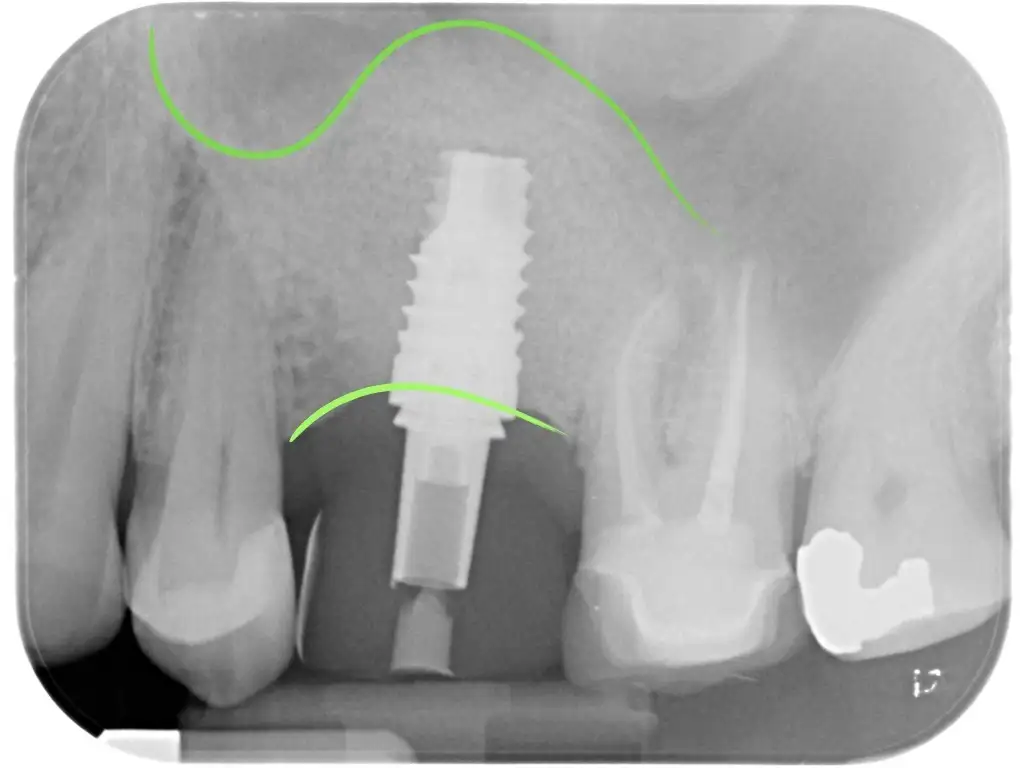

I nuovi impianti che abbiamo a disposizione di lunghezza ridotta con particolari superfici ci permettono in molti casi di evitare interventi rigenerativi nonostante l’altezza ossea sia ridotta.

Ci sono di grande aiuto soprattutto nella mandibola posteriore dove diventano molto vantaggiosi rispetto a lunghi interventi di rigenerazione.

Ciò consente di accorciare i tempi ed essere ancora una volta mininvasivi.